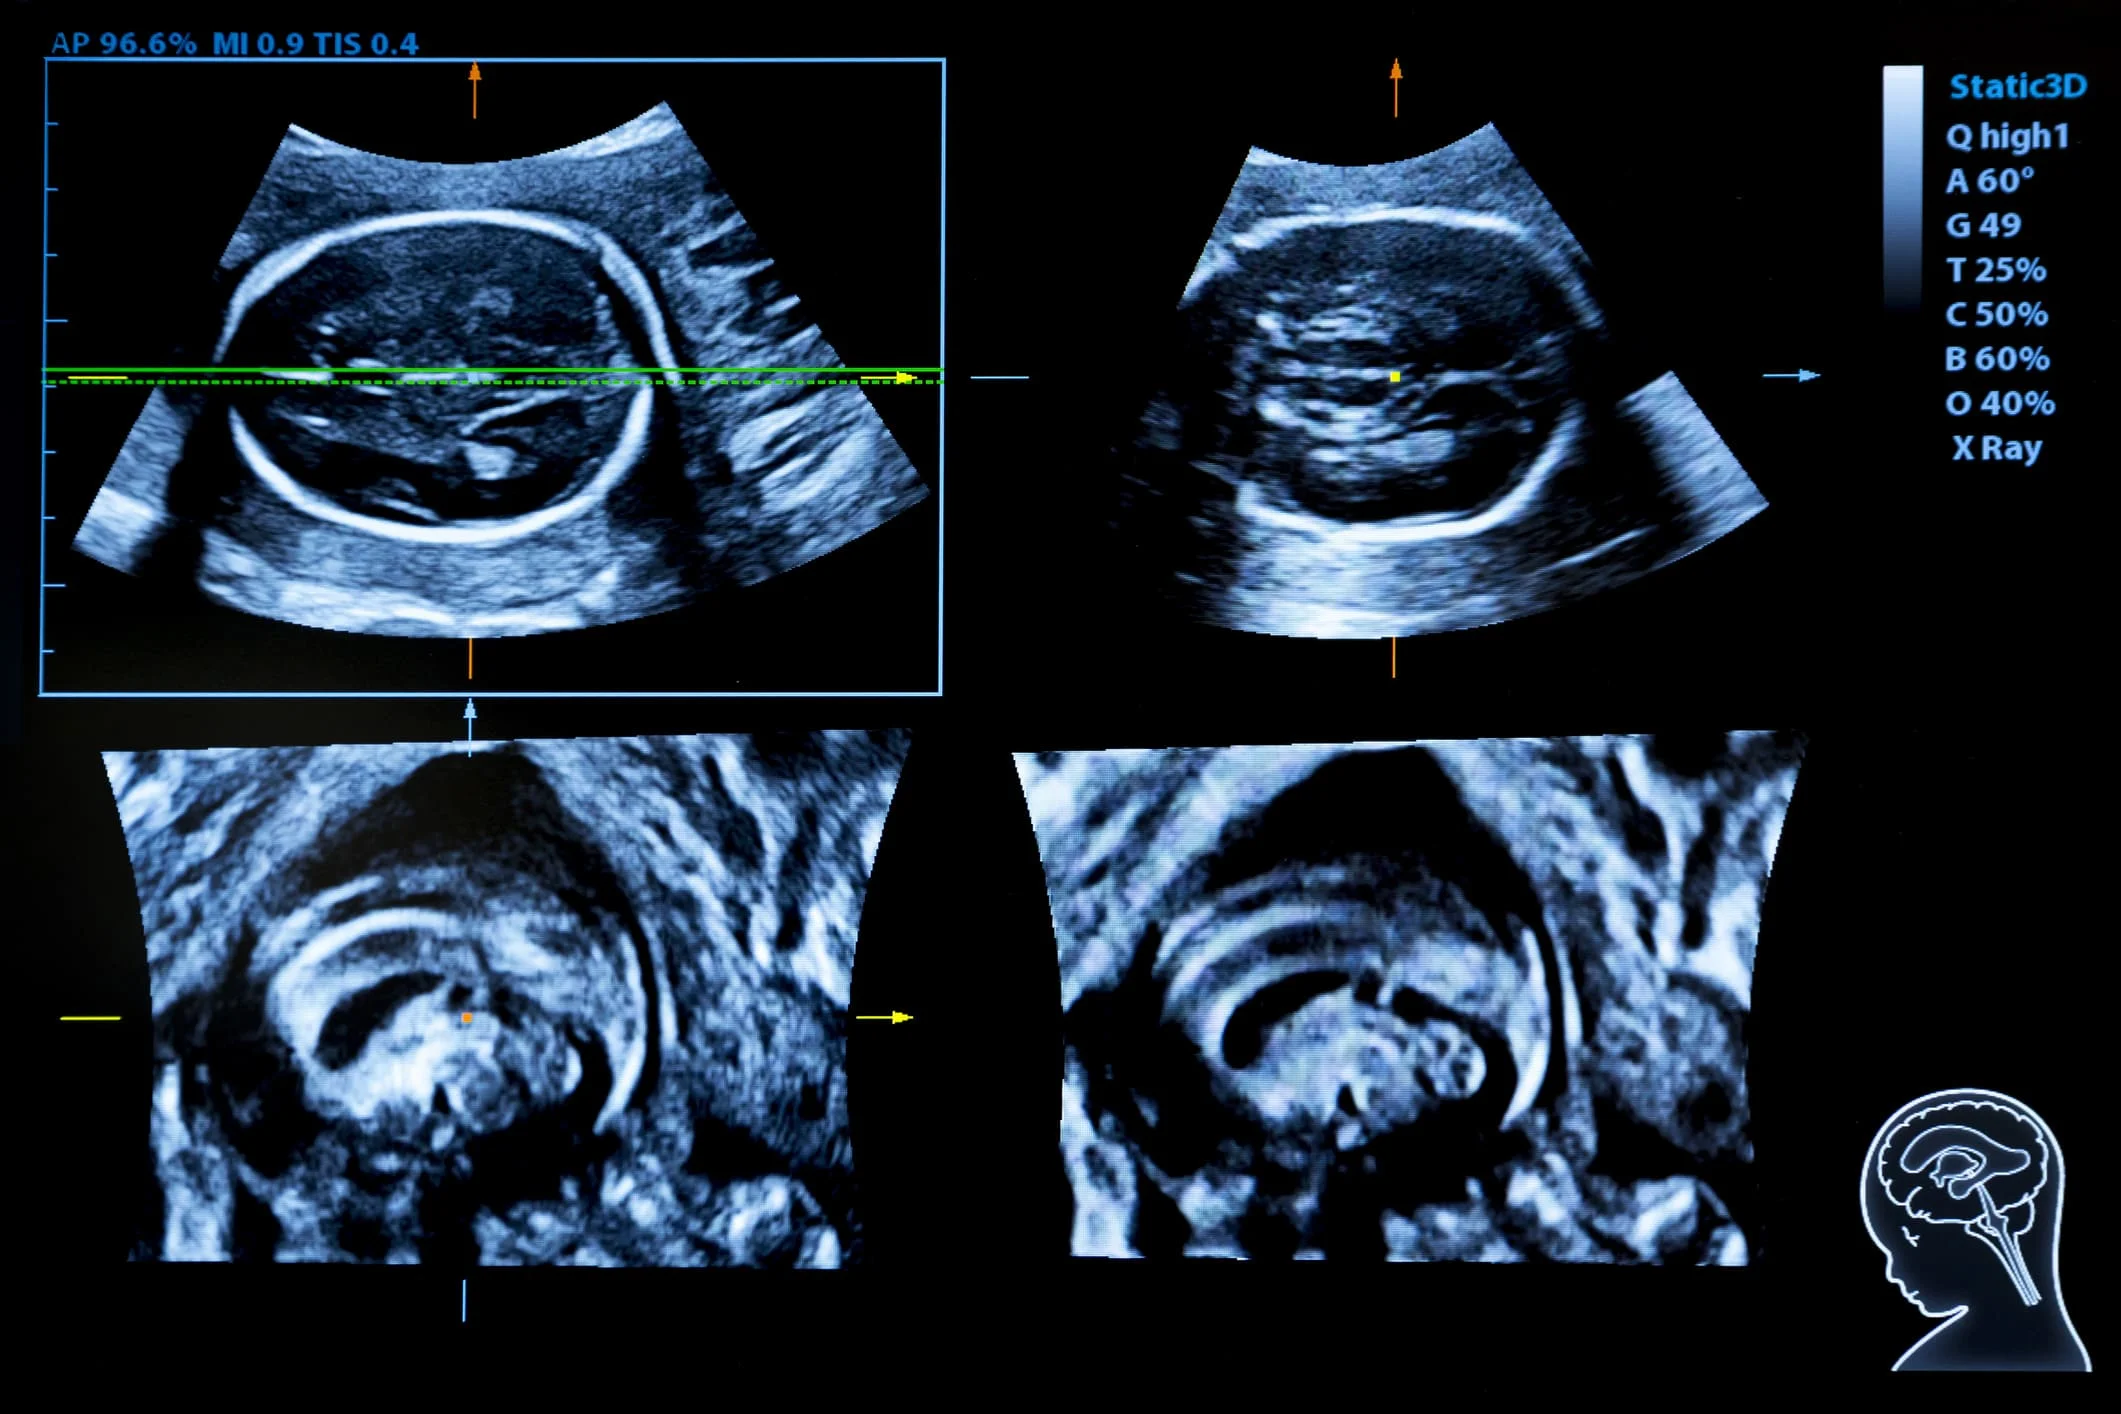

Neurosonografía fetal

La neurosonografía fetal es una técnica de ultrasonido especializada que permite evaluar de manera detallada el desarrollo del sistema nervioso central del bebé durante el embarazo. Esta prueba